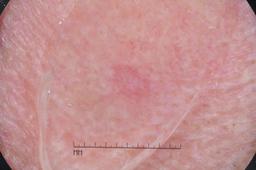

{

"age_approx": 80,

"anatom_site_general": "head/neck",

"concomitant_biopsy": true,

"diagnosis_1": "Malignant",

"diagnosis_2": "Malignant adnexal epithelial proliferations - Follicular",

"diagnosis_3": "Basal cell carcinoma",

"diagnosis_confirm_type": "histopathology",

"image_type": "dermoscopic",

"lesion_id": "IL_0657178",

"melanocytic": false,

"sex": "female"

}